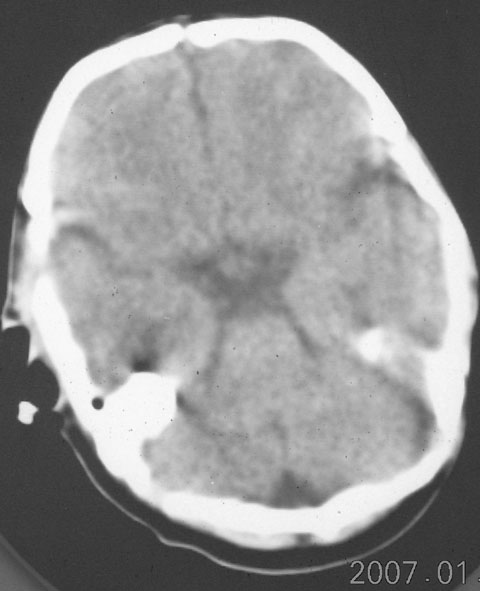

以下是引用rjg199343在2007-1-24 23:08:00的发言:[br]纵裂池、小脑幕、双侧脑室内高密度影,符合脑室、蛛网膜下腔出血。

以下是引用jiangjing在2007-1-24 23:31:00的发言:[br]纵裂池、小脑幕、双侧脑室内高密度影,符合脑室、蛛网膜下腔出血